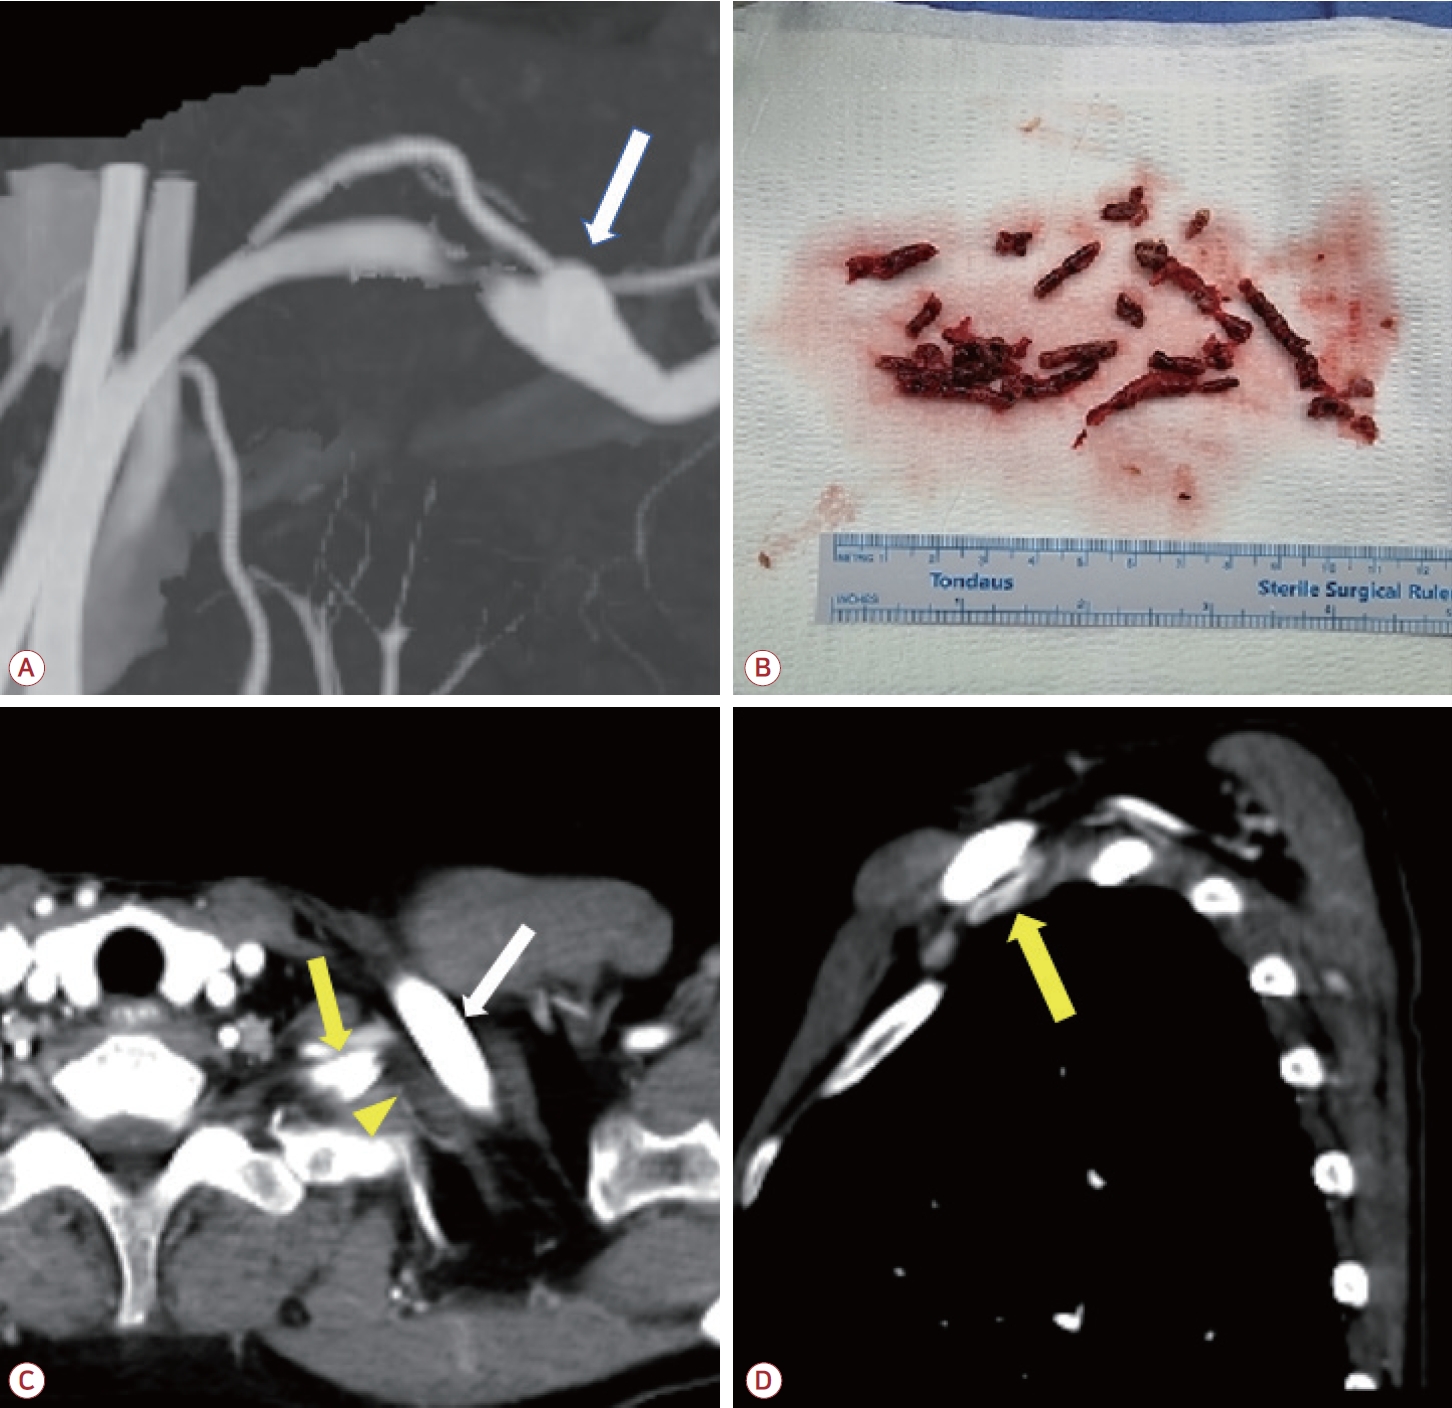

환자는 좌측 쇄골하동맥 폐색 및 동반된 뇌경색에 대해 입원하여 저분자량헤파린인 에녹사파린(enoxaparin) 1 mg/kg 하루 두 번으로 항응고 치료를 시작하였고 입원 3일차에 쇄골하동맥의 혈전색전제거술(thromboembolectomy)을 시행하였다(Fig. 2-B). 시술 후에 환자는 추가적인 뇌경색 병변이 발견되지 않았고 좌측 상지의 청색증이 호전되었으며 혈압 또한 우측과 차이를 보이지 않았다. 이후 에픽사반(apixaban) 5 mg 하루 두 번으로 약물 교체 이후 퇴원하였다. 시술 3개월 이후 추적 관찰한 혈관조영에서 이전에 보였던 혈전은 모두 제거되었고 새로운 혈전이 발생하지 않았음을 확인하였다. 또한 좌측 경추 늑골과 쇄골에 의한 쇄골하동맥의 압박 소견 및 이로 인한 말초 동맥류가 관찰되었다(Fig. 2-A, C, D). 이에 환자는 aTOS로 인한 뇌경색으로 최종 진단할 수 있었다. 환자는 항혈소판제인 아스피린 하루 100 mg으로 약물을 교체하였다. 환자에게 흉곽 출구증후군에 대해 경추늑골제거술 및 혈관성형술 등 수술적 치료를 권유하였으나 거절하여 약물 복용 유지 중에 있다.

본 증례의 환자는 뇌경색 증상 이전에 우측 상지의 감각 증상 및 청색증이 나타났고 이후 어지러움 및 이명 등의 증상이 나타났다. 시행한 영상 검사에서는 뇌 후순환 영역의 여러 부위에 색전성 뇌경색 및 좌측 쇄골하동맥의 혈전 및 폐색이 확인되었다. 혈역학적으로 상소뇌동맥 및 전하소뇌동맥은 좌우 척추동맥이 합쳐져 형성된 뇌기저동맥에서 기시한다. 또한 환자의 우측 척추동맥저형성증을 고려할 때 좌측 척추동맥에서 공통 후하소뇌동맥이 분지하는 해부학적 변이가 존재할 가능성이 높다[8]. 이를 종합적으로 고려하면 우측 소뇌 영역을 포함한 뇌경색 병변은 좌측 쇄골하동맥 내 혈전이 색전의 기원으로 작용하였을 가능성이 높다고 판단하였다. 또한 추적 검사에서 경추 늑골의 쇄골하동맥 압박 및 쇄골하동맥류가 확인되어 aTOS 및 이로 인한 급성 뇌경색으로 진단할 수 있었다.